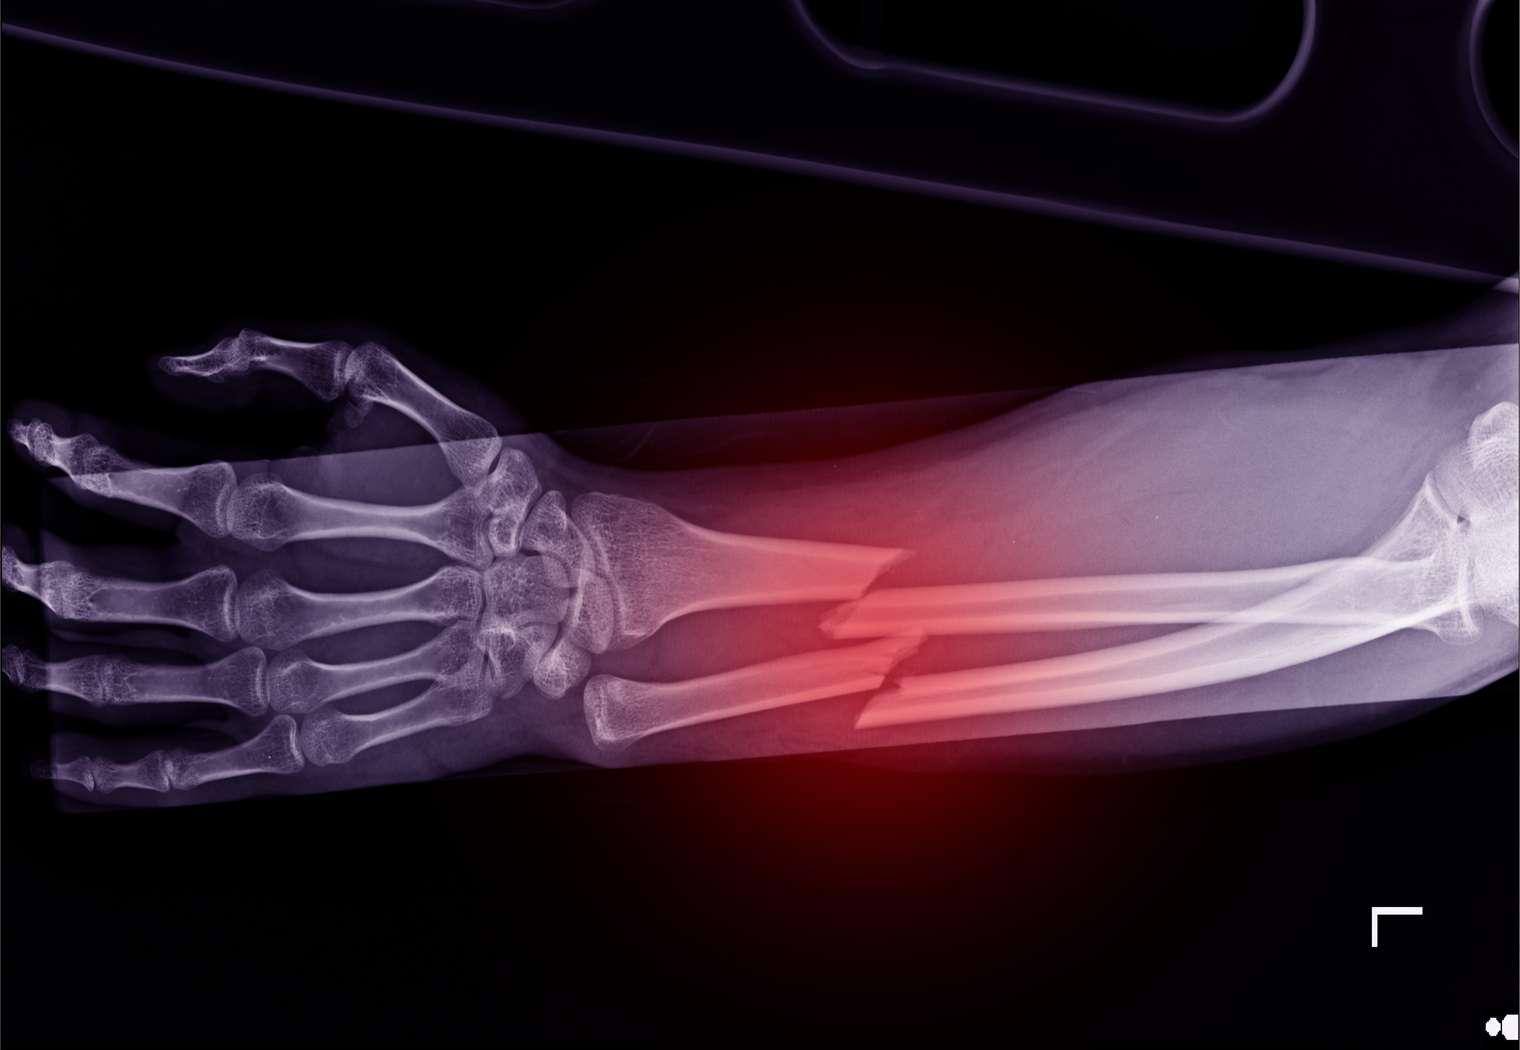

Le second est un essai auxiliaire randomisé (avec une randomisation factorielle) en triple aveugle contre placebo. L’essai principal (VITAL) avait pour objectif de déterminer l’effet d’une prise d’oméga 3 d’un côté et de vitamine D de l’autre sur la prévention des maladies cardiovasculaires et du cancer. L’essai auxiliaire dont il est question s’est concentré sur le risque de fracture autodéclarée comme critère de jugement. Chez plus de 25.000 patients américains non dépistés pour une carence en vitamine D, le risque de fracture n’a pas été réduit par la prise de vitamine D.

La prise de vitamine D ne semble pas avoir d’effet sur la mortalité, ni sur le risque de fracture chez les personnes de plus de 60 ans sans diagnostic de carence. Il convient alors d’être prudent avec la prise de compléments alimentaires dépourvus de certains bénéfices, car les risques peuvent parfois être mal évalués, comme le suggère la récente enquête ouverte sur le curcuma. Évidemment, ces essais ne disent rien sur l’efficacité de la vitamine D dans d’autres indications et chez d’autres types de patients.